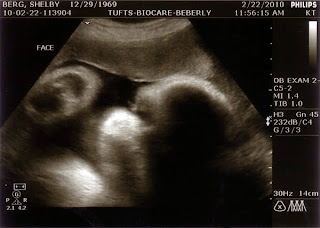

I followed up my 35 week appointment with another ultrasound today. Because of Riley's prenatal stroke, they wanted another look at Kendall now that she's almost full-term (37 weeks). Since Jonathan and I were tested for any genetic clotting factors (negative), I wasn't too concerned. I was more interested in getting confirmation of whether or not Kendall was still in breech position as she was two weeks ago. My midwife said it was difficult to tell from feeling around my belly.

We were relieved to find out that Kendall is head down..Thank you, Jesus. So I guess what I thought was her head must have been her bum. I'm thankful to have one less thing to be concerned about.

We also found out that Kendall's estimated weight is 6 lbs. That means, I'm on the way of delivering an 8 lb baby if Kendall arrives sometime after 39 weeks. Oy. Maybe I should put this girl on a diet now.

The ultrasound technician also said she has a head of hair on her (as Riley and I did as newborns), so we're pretty excited about seeing those beautiful locks next month. We're going to need a frequent user card at Snip-Its if her hair grows as fast as Riley's does.

We got a facial shot showing her cute little chubby cheeks to share with you: